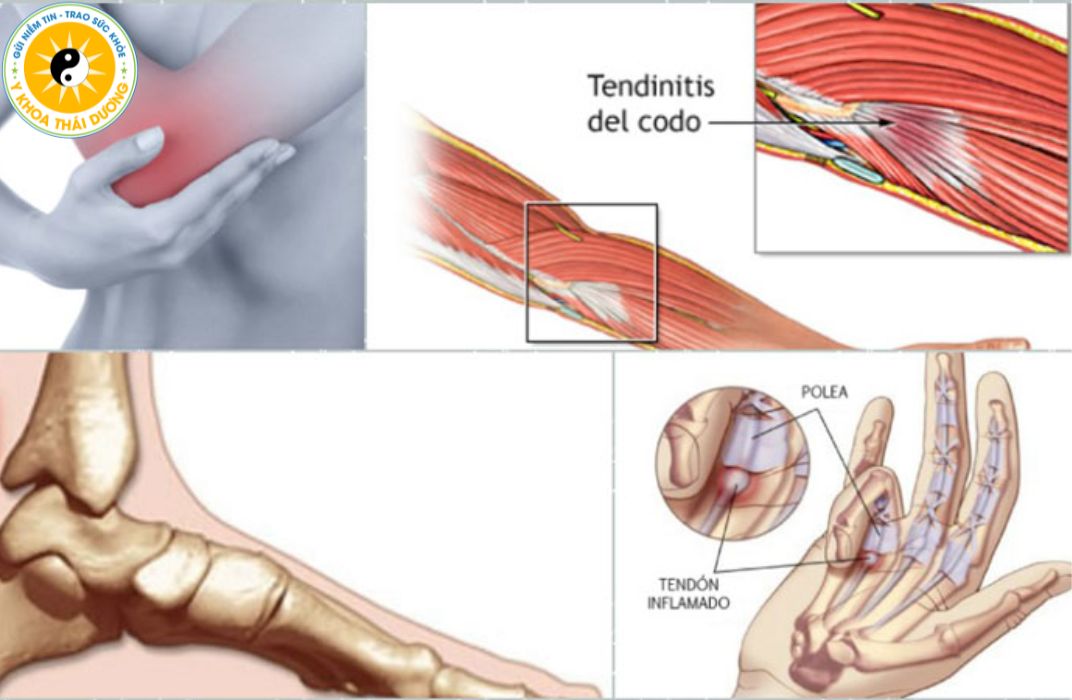

Viêm gân: Nguyên nhân, triệu chứng và phương pháp điều trị

Viêm gân (Tendinitis) là bệnh lý cơ xương khớp xảy ra rất phổ biến ở...

Viêm gân: Làm sao để điều trị dứt điểm và tránh tái phát?

Viêm gân là tình trạng tổn thương phổ biến gây đau nhức và hạn chế...